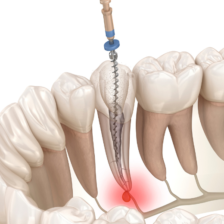

根管治療の成功率を上げるためには、知識や経験はもちろんですが、精密な治療に対応するための設備や器具も不可欠です。

当院では、歯科用顕微鏡(マイクロスコープ)や歯科用CBCT、ラバーダム、ニッケルチタンファイルなど、患者さんにより良い治療を提供するための設備・器具を揃えております。